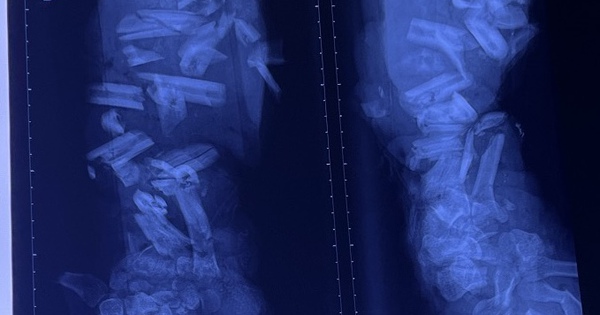

Ca tai nạn lao động thương tâm: Cánh tay bị máy nghiền vỏ dừa nghiền nát

Tai nạn lao động xảy ra khá thường xuyên, nhưng nhiều người vẫn còn chủ quan dẫn đến những thương tích đáng tiếc, thậm chí tử vong.